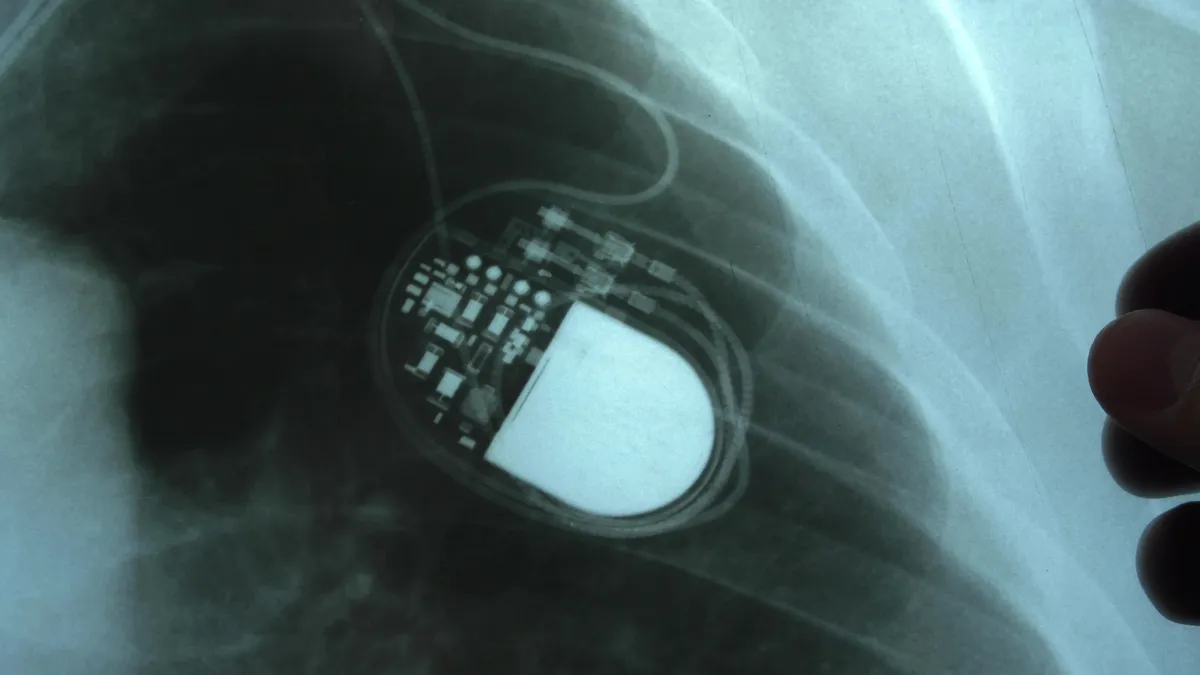

A pacemaker beültetés általában helyi érzéstelenítésben történik, és a legtöbb esetben nem igényel altatást. A beavatkozás során a készüléket a kulcscsont alatti területre ültetik be, majd vékony vezetékeket juttatnak a vénákon keresztül a szív megfelelő üregeibe.

A műtét általában egy-két órát vesz igénybe. A beültetés után a készülék működését azonnal ellenőrzik, és beállítják az egyéni szükségletekhez igazodva. A kórházi tartózkodás többnyire rövid, komplikációmentes esetben akár néhány nap alatt hazaengedhető a beteg.